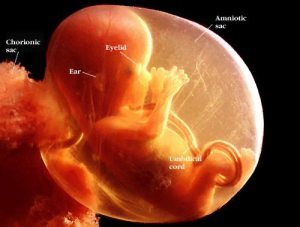

During my time there, I cared for women during their pregnancies, including when they miscarried. I remember one woman came in to confirm her miscarriage and brought the passed tissues in a baggie. I think that she was about 11-12 weeks along. The baggie was given to the nurses so that we could send the tissues to the lab. In the bag, there was a perfectly round circle of tissue (about the size of a half dollar). The nurses gathered around and we held it up to the light. We could see an amazing outline of a baby. I will never forget that image. My heart ached for the woman and for the tiny baby that I held in my hand.